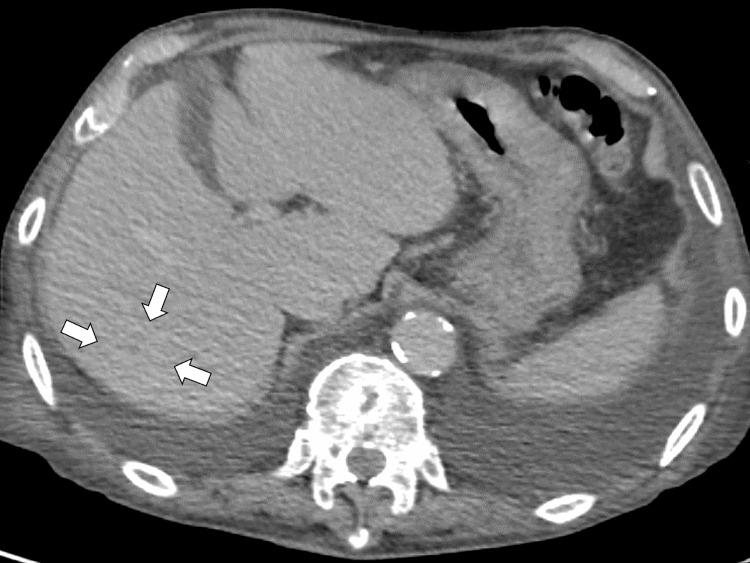

一名患有多种合并症的82岁男性因发热和活动能力下降前往一家乡村医院就诊,被诊断为高毒力肺炎克雷伯菌(HVKP)所致的肝脓肿。最初采用静脉抗生素治疗使影像学表现有所改善,但患者出现复发性菌血症、腰痛,最终发展为硬膜外脓肿、感染性心内膜炎和脑脓毒性栓子。尽管升级了抗生素治疗并给予支持治疗,但其病情仍恶化,由于严重脓毒症和心力衰竭,手术干预被认为不可行。他于住院第27天死亡。该病例凸显了HVKP感染的诊断和治疗挑战,尤其是在患有基础疾病的老年人中。即使早期治疗且原发性脓肿得到明显控制,HVKP仍可经血行播散,导致严重并发症。临床医生应高度怀疑其发生全身播散,并考虑延长治疗时间和加强监测,尤其是在老年或免疫功能低下的患者中。